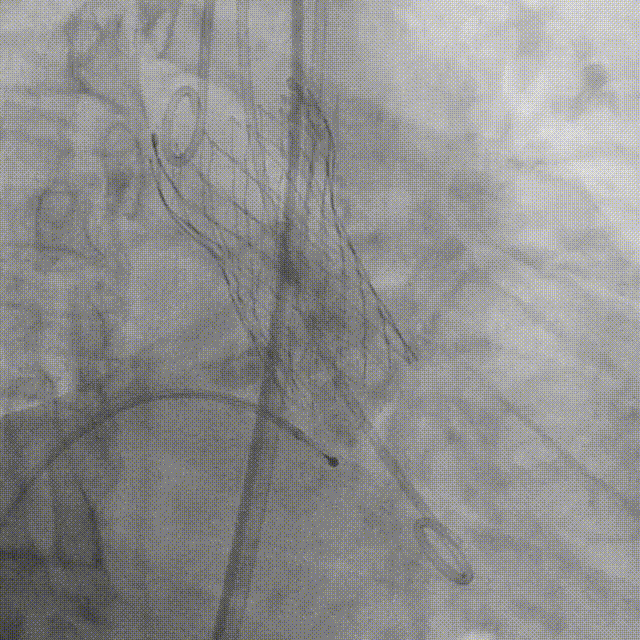

20mm球囊第一次预扩张 钙化太重,球囊卡腰征

20mm球囊第二次预扩张 球囊完全扩张开,达到扩张目的